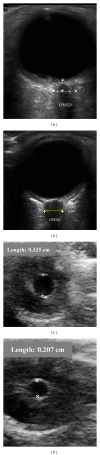

Ultrasound is a safe, portable, relatively inexpensive, and easily accessible imaging modality, making it a useful diagnostic and monitoring tool in medicine. Anesthesiologists encounter a variety of emergent situations and may benefit from the application of such a rapid and accurate diagnostic tool in their routine practice. This paper reviews current and potential applications of ultrasound in anesthesiology in order to encourage anesthesiologists to learn and use this useful tool as an adjunct to physical examination. Ultrasound-guided peripheral nerve blockade and vascular access represent the most popular ultrasound applications in anesthesiology. Ultrasound has recently started to substitute for CT scans and fluoroscopy in many pain treatment procedures. Although the application of airway ultrasound is still limited, it has a promising future. Lung ultrasound is a well-established field in point-of-care medicine, and it could have a great impact if utilized in our ORs, as it may help in rapid and accurate diagnosis in many emergent situations. Optic nerve sheath diameter (ONSD) measurement and transcranial color coded duplex (TCCD) are relatively new neuroimaging modalities, which assess intracranial pressure and cerebral blood flow. Gastric ultrasound can be used for assessment of gastric content and diagnosis of full stomach. Focused transthoracic (TTE) and transesophageal (TEE) echocardiography facilitate the assessment of left and right ventricular function, cardiac valve abnormalities, and volume status as well as guiding cardiac resuscitation. Thus, there are multiple potential areas where ultrasound can play a significant role in guiding otherwise blind and invasive interventions, diagnosing critical conditions, and assessing for possible anatomic variations that may lead to plan modification. We suggest that ultrasound training should be part of any anesthesiology training program curriculum.